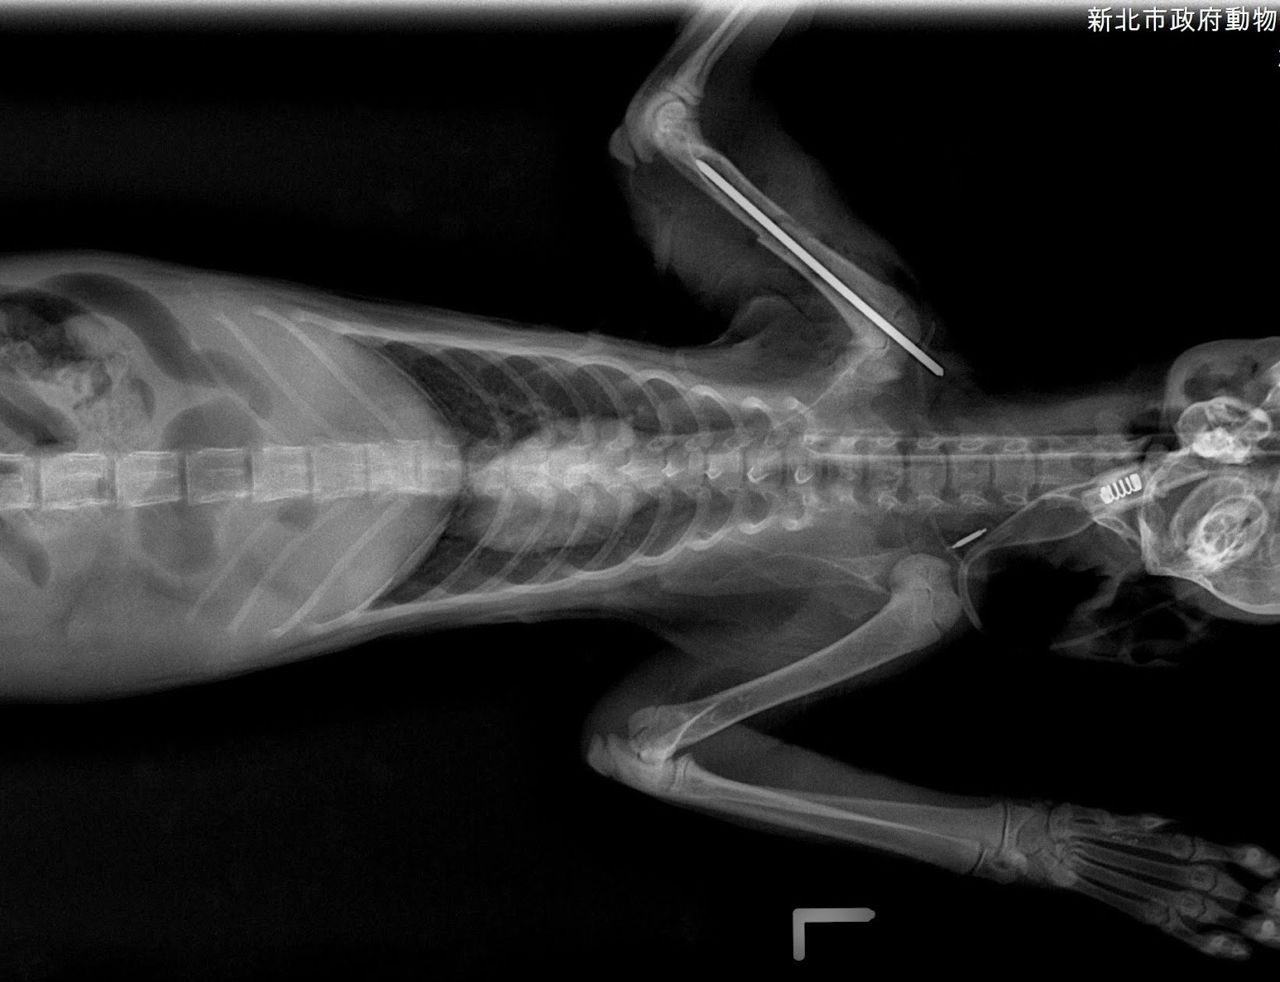

新北市動保處日前接獲通報,新店區安祥路有隻虎斑白貓,疑似車禍受傷,臉部充滿血漬

癱臥路旁,動保處隨即派員帶回檢傷醫療,發現虎斑白貓上顎有傷口、右前肢蜷縮無法撐

地,X光檢查下發現右前肢肱骨交錯性骨折,肺部支氣管炎症反應嚴重,所幸經過緊急輸

液、給氧及骨科手術治療後已恢復健康。

動保處獸醫幫虎斑白貓「萌萌」照X光發現右前肢肱骨交錯性骨折。圖/新北市動保處提

供